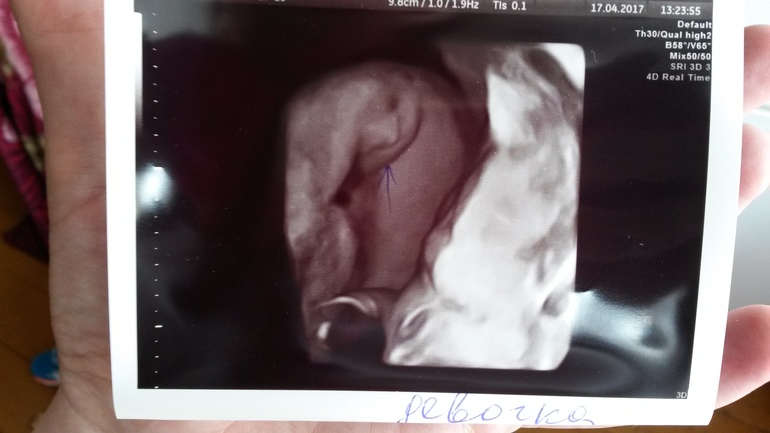

В общем говорят мне что все хорошо у нас,единственное - пуповина на шее...Однократное обвитие...

Я так и знала что моя шилопопка намотает ее на себя(((Врач начинает записывать ролики и моя козявка ложит руку на правый глаз,и обе ноги ко лбу!!!!!!И все!!!Ни в какую не уберает ни ноги ни руку!!!Я уже и кашляла и крутили меня во все стороны - бесполезно вообще!!!

Ну и наши фото!Доказательство что это Виктория,а не Витя)))